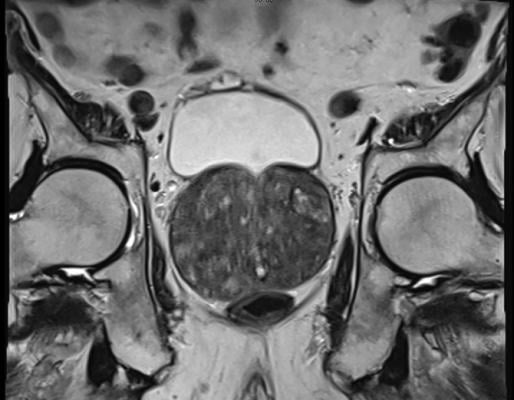

Benign Prostatic Hyperplasia (BPH) or prostate adenoma seen on MRI examination. Getty Images